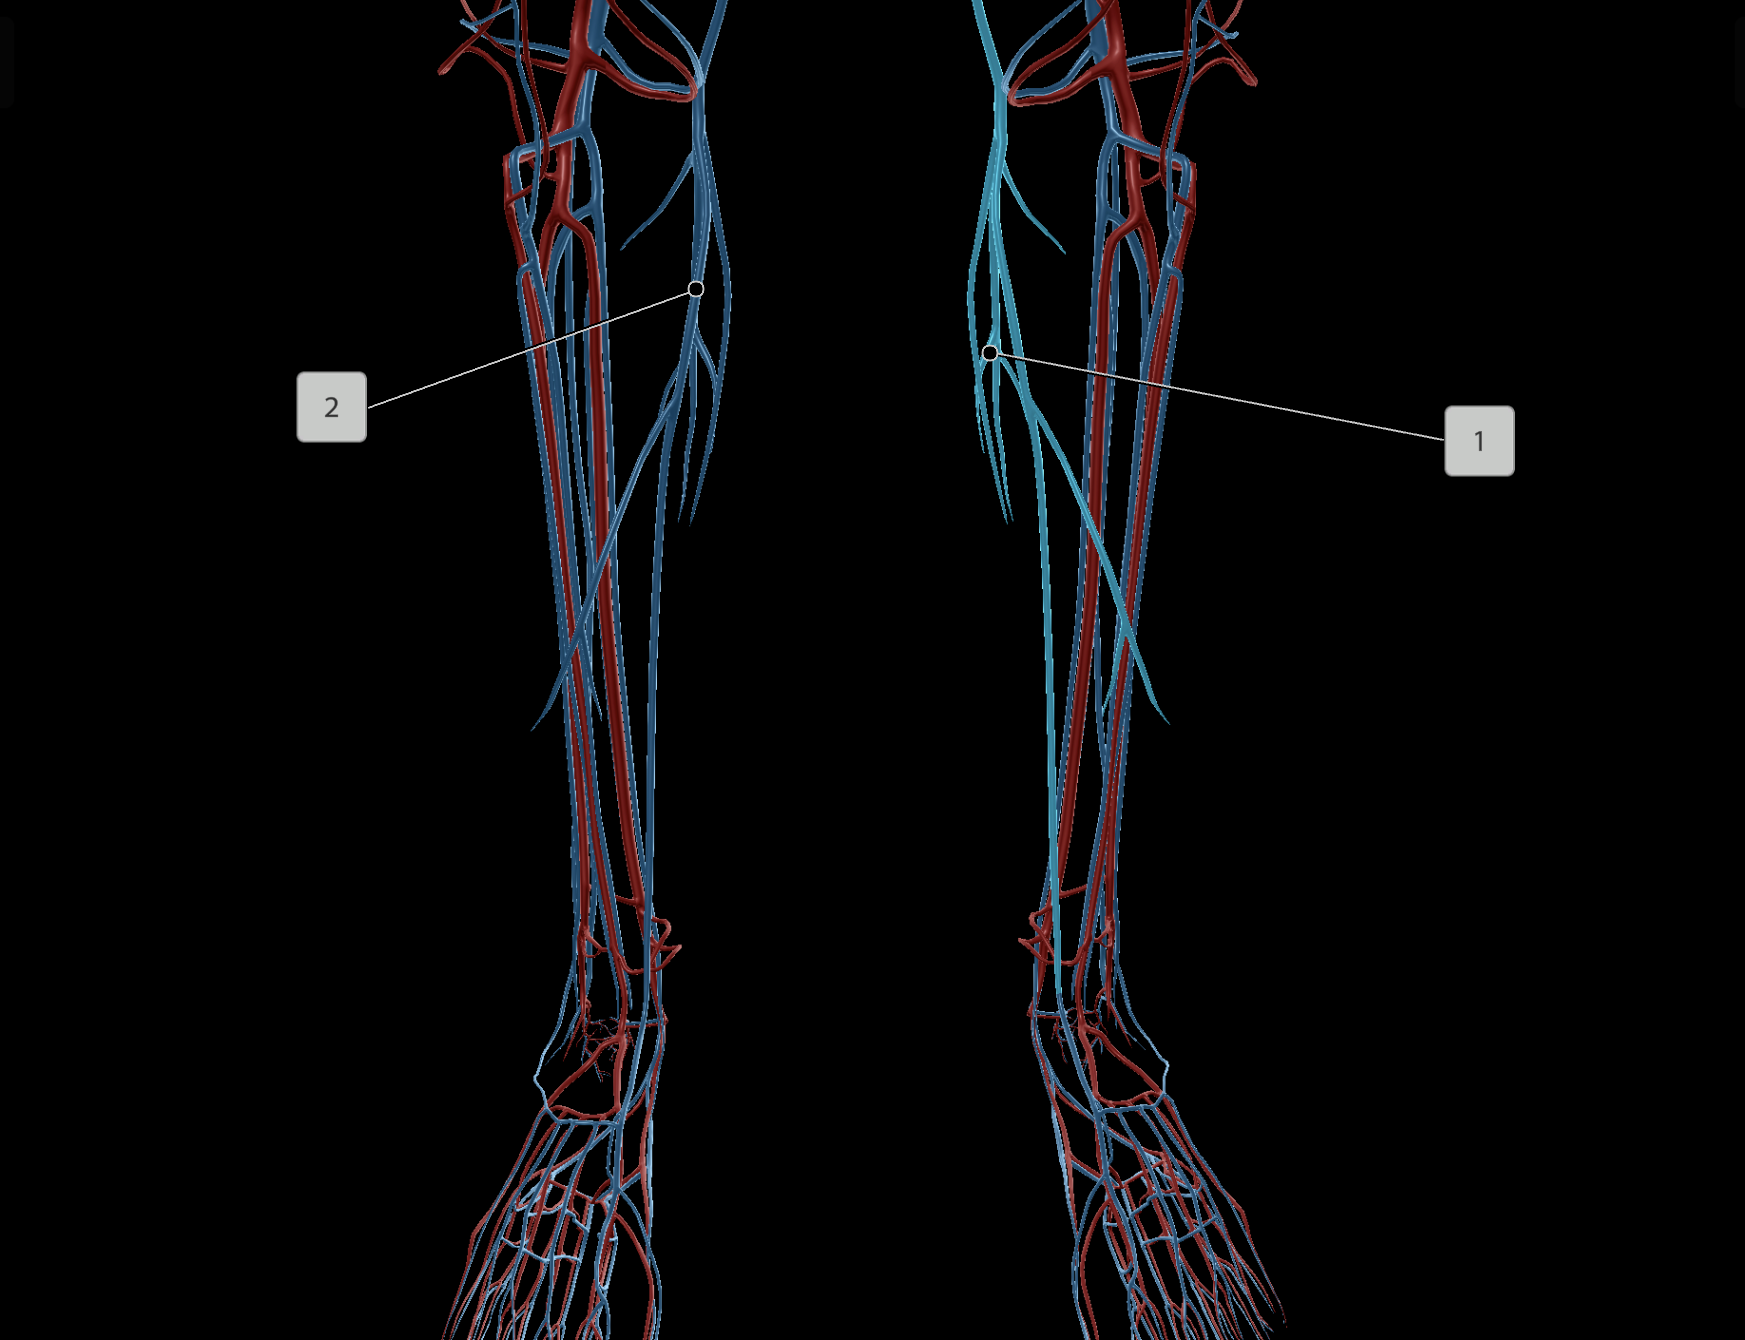

Anterior Tibial Artery

Posterior Tibial Artery

Femoral Artery

Popliteal Artery

Femoral Vein

Popliteal Vein

Anterior Tibial Vein

Posterior Tibial Vein

Great Saphenous Vein

Deep Femoral Artery

Peroneal Artery